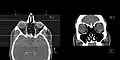

CT scan of the paranasal sinuses with coronal reconstruction (right) and axial planning data (left). -